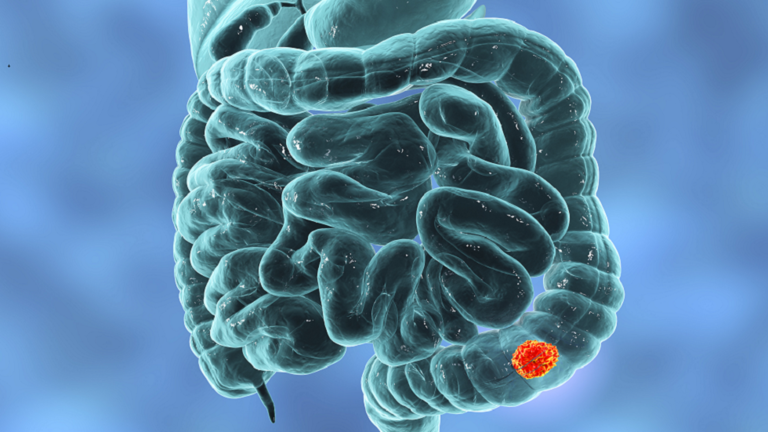

إنجلترا – تشمل أعراض سرطان الأمعاء فقدان الوزن وتغيير عادة استخدام المرحاض والشعور بالتعب الشديد دون سبب واضح.

ويعد سرطان الأمعاء أحد أكثر أنواع السرطان شيوعا، وينبغي أن تفكر في التحدث إلى الطبيب، إذا وجدت أن لون برازك مختلف عن اللون الطبيعي، وفقا لخبراء الصحة.

ومن أولى العلامات التحذيرية لسرطان الأمعاء، وجود براز داكن اللون أكثر مما اعتدت عليه. وقد يكون لون برازك أحمر، أو يبدو بلون أحمر غامق جدا، وفقا لجمعية MacMillan Cancer Support الخيرية.

ويأتي اللون نتيجة مباشرة لنزيف في منطقة الظهر، أو أعلى في الأمعاء. وقد يجد بعض الناس أن برازهم أحمر فاتح، وقد يكون سبب ذلك البواسير أيضا.

وقالت الجمعية الخيرية إن علامات وأعراض سرطان الأمعاء قد تعتمد على نوع معين لديك، وقد تشمل الأعراض وجود دم في برازك أو فوقه أو نزيف من الممر الخلفي [المستقيم]. وقد يكون الدم أحمر فاتحا أو غامقا.

وفي حال عانيت من أعراض لا تتحسن في غضون أسابيع قليلة، أو إذا ساءت الأعراض، فمن المهم أن تتم إحالتك إلى أخصائي.

ولكن، لمجرد اكتشاف وجود دم في برازك، فهذا لا يعني بالضرورة أنك مصاب بسرطان الأمعاء.

وقالت إدارة الصحة الوطنية البريطانية إن كمية صغيرة من الدم لمرة واحدة لا تنتج عادة عن أي شيء خطير. وقد يكون ناتجا عن التهاب المعدة والأمعاء أو ورم الأمعاء أو البواسير أو الشق الشرجي.

وتحدث أكثر من 90% من جميع أسباب سرطان الأمعاء، لدى الأشخاص فوق سن الخمسين. ويمكنك تقليل خطر الإصابة بالمرض عن طريق تقليل كمية الكحول في نظامك الغذائي، والإقلاع عن التدخين.